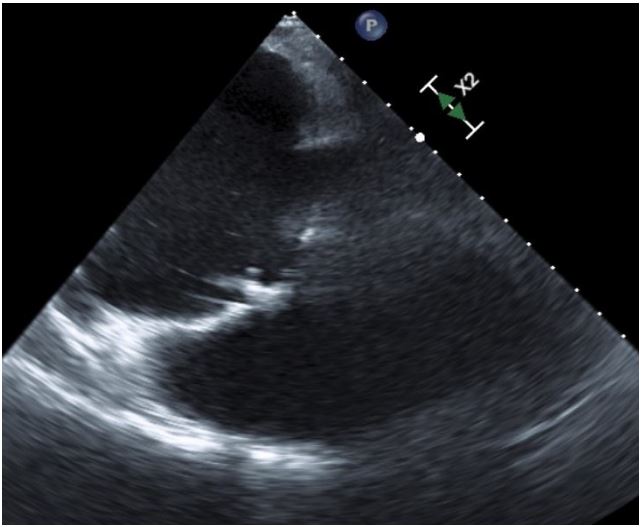

Echocardiogram (Figures 1,2) and MRI (Figure 3) showed severe dilation of the right atrium, severe tricuspid regurgitation, decreased ventricular systolic dysfunction, and dilated right ventricle. Based on his echocardiogram & MRI, it was determined that he would benefit from a tricuspid valve replacement. Preoperative type and cross was positive for cold agglutinin and needed appropriately matched blood.

Figure 1: Pre Op TEE showing tricuspid ring, dilated RA and RV.